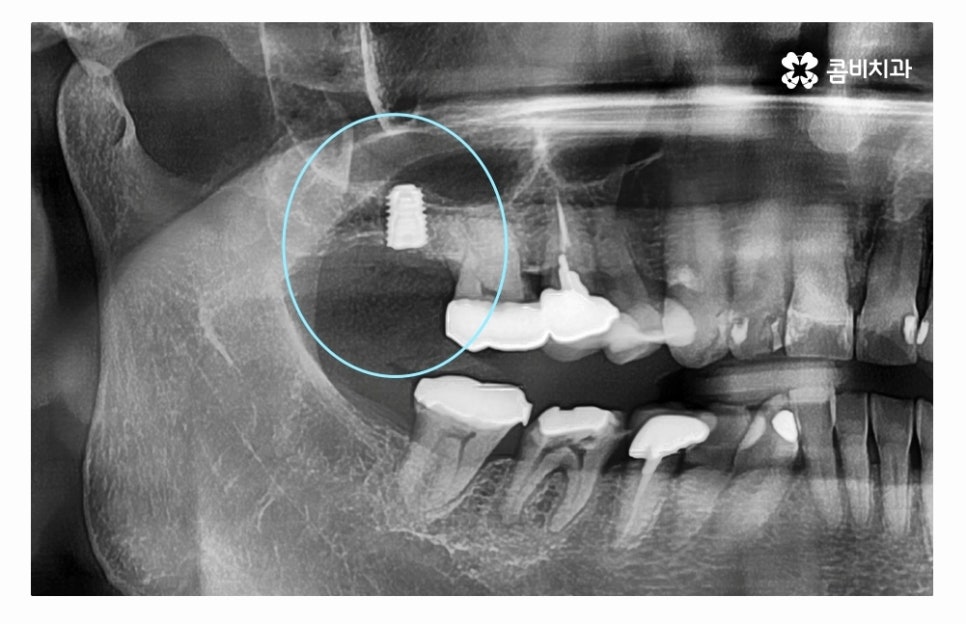

오늘 소개드릴 사례의 경우 충치로 인해 치아를 잃게 되었으며

발치 후 임플란트 수술을 통해 치아의 기능을 수복하였는데

치아를 잃게 되었을 때 원인을 잘 찾고 반복된 문제가 발생하지

않도록 정확한 진단이 필요하다고 할 수 있어요.

임플란트수술의 원리는 잇몸 뼈에 인공 치근을 식립하고

지대주로 단단하게 고정력을 얻은 후에 보철물을 연결하여

치료를 마무리하게 되는데 자연치아도 그렇듯이

임플란트 역시도 잇몸 뼈의 상태가 매우 중요하다고 할 수 있는데요.